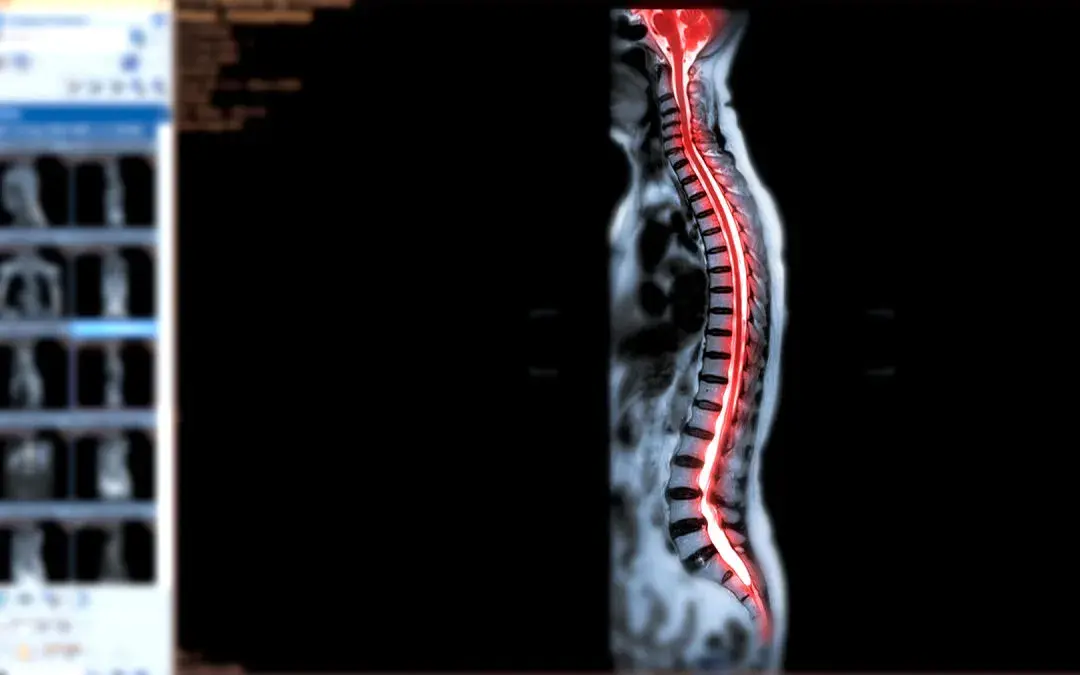

An MRI (Magnetic Resonance Imaging) whole spine screening is a non-invasive diagnostic procedure that uses powerful magnets and radio waves to generate detailed images of our entire spine.

Unlike X-ray and CT scans, which provide limited information, an MRI scan captures high-resolution images, allowing healthcare professionals to assess the anatomy of the spine, discs, nerves, and surrounding soft tissues.

Understanding the intricate anatomy of our spine and brain provides context and significance to the remarkable capabilities of a whole spine MRI screening. By harnessing the power of magnetic resonance imaging, this diagnostic procedure allows us to capture detailed images of our spine, revealing its inner workings with astonishing clarity.

It enables healthcare professionals to assess the health of our vertebrae, discs, spinal cord, and nerves, guiding them in diagnosing and treating various spinal conditions.